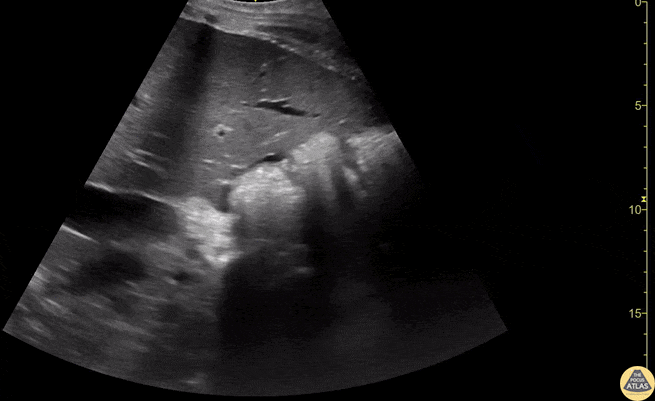

Free fluid demonstrated at the liver tip in a patient with ascites. The liver tip is the most sensitive part of the RUQ for free fluid. In the context of blunt trauma this would be concerning for bleeding. Contributors: Dimitri Livshits, DO; Jane Belyavskaya, MD; Chris Hanuscin, MD Kings County/SUNY Downstate